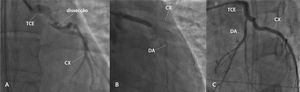

Foi encaminhada para cineangiocoronariografia de urgência, que revelou lesão suboclusiva, com aspecto de dissecção espontânea em tronco de coronária esquerda, com fluxo mínimo nas artérias descendente anterior e circunflexa (fig. 1A). Foi imediatamente submetida à intervenção coronária percutânea primária com implante de um stent não farmacológico no tronco de coronária esquerda (fig. 1B e 1C). Durante o procedimento, apresentou cinco novos episódios de parada cardiorrespiratória em ritmo de atividade elétrica sem pulso, prontamente revertidas.

(A) Lesão com aspecto de dissecção espontânea em tronco de coronária esquerda (TCE), com fluxo mínimo nas artérias descendente anterior (DA) e circunflexa (CX). (B) Intervenção coronária percutânea com implante de um stent não farmacológico em TCE. (C) Resultado após a intervenção coronária percutânea.